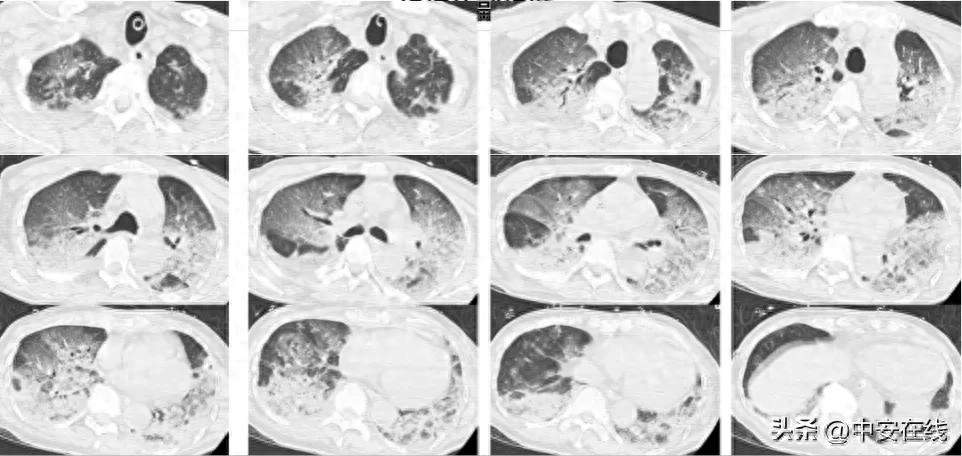

11时45分,桂奶奶在亲人家属的协助下,火速被送达武汉脑科医院·长江航运总医院。抵达医院时,她意识不清,呈现恶心、排泄失控,且右侧身体完全麻痹。该院迅即启动了卒中急救绿色通道,急诊CT检查排除了脑出血风险,接诊医生迅速诊断为急性脑梗塞,并紧急联系神经内科卒中急救小组进行救治。

生命重于时间,院方医疗团队即刻响应。于12时13分,神经内科值班医师谭建军为桂奶奶施行了静脉溶栓治疗。从入院至治疗完毕,耗时仅28分钟,桂奶奶的生命体征即恢复稳定。在整个救治过程中,医护人员动作迅速且精确,每一秒均是抢救生命的宝贵时间。